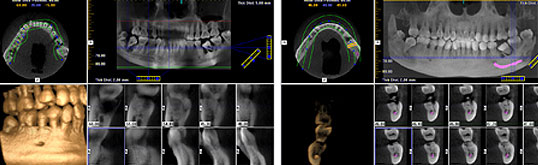

Anhand der dreidimensionalen Ansichten Ihres Kiefers können wir die Implantation am Computer simulieren. |

- welche Implantate verwendet werden sollten,

- und welche Position im Kiefer und welcher Neigungswinkel die besten funktionalen und ästhetischen Ergebnisse versprechen.

Anhand dieser Daten kann unser Dentallabor eine Schablone herstellen, mit der die Implantate während des Eingriffes exakt an der vorausberechneten Stelle eingesetzt werden.

Die Implantation verläuft schneller und in der Regel schonender. Häufig sind nur wenige kleine Schnitte durch das Zahnfleisch notwendig. Dadurch werden Schwellungen und Beschwerden reduziert. Außerdem können wir die Implantation auch bei schwierigen Voraussetzungen exakt planen und durchführen.

Auch die Entfernung von verlagerten Weisheitszähnen lässt sich so umfassend planen. Wir sehen, wie wir vorgehen müssen, um Nerven und andere empfindliche Strukturen bei dem Eingriff sicher zu schützen.